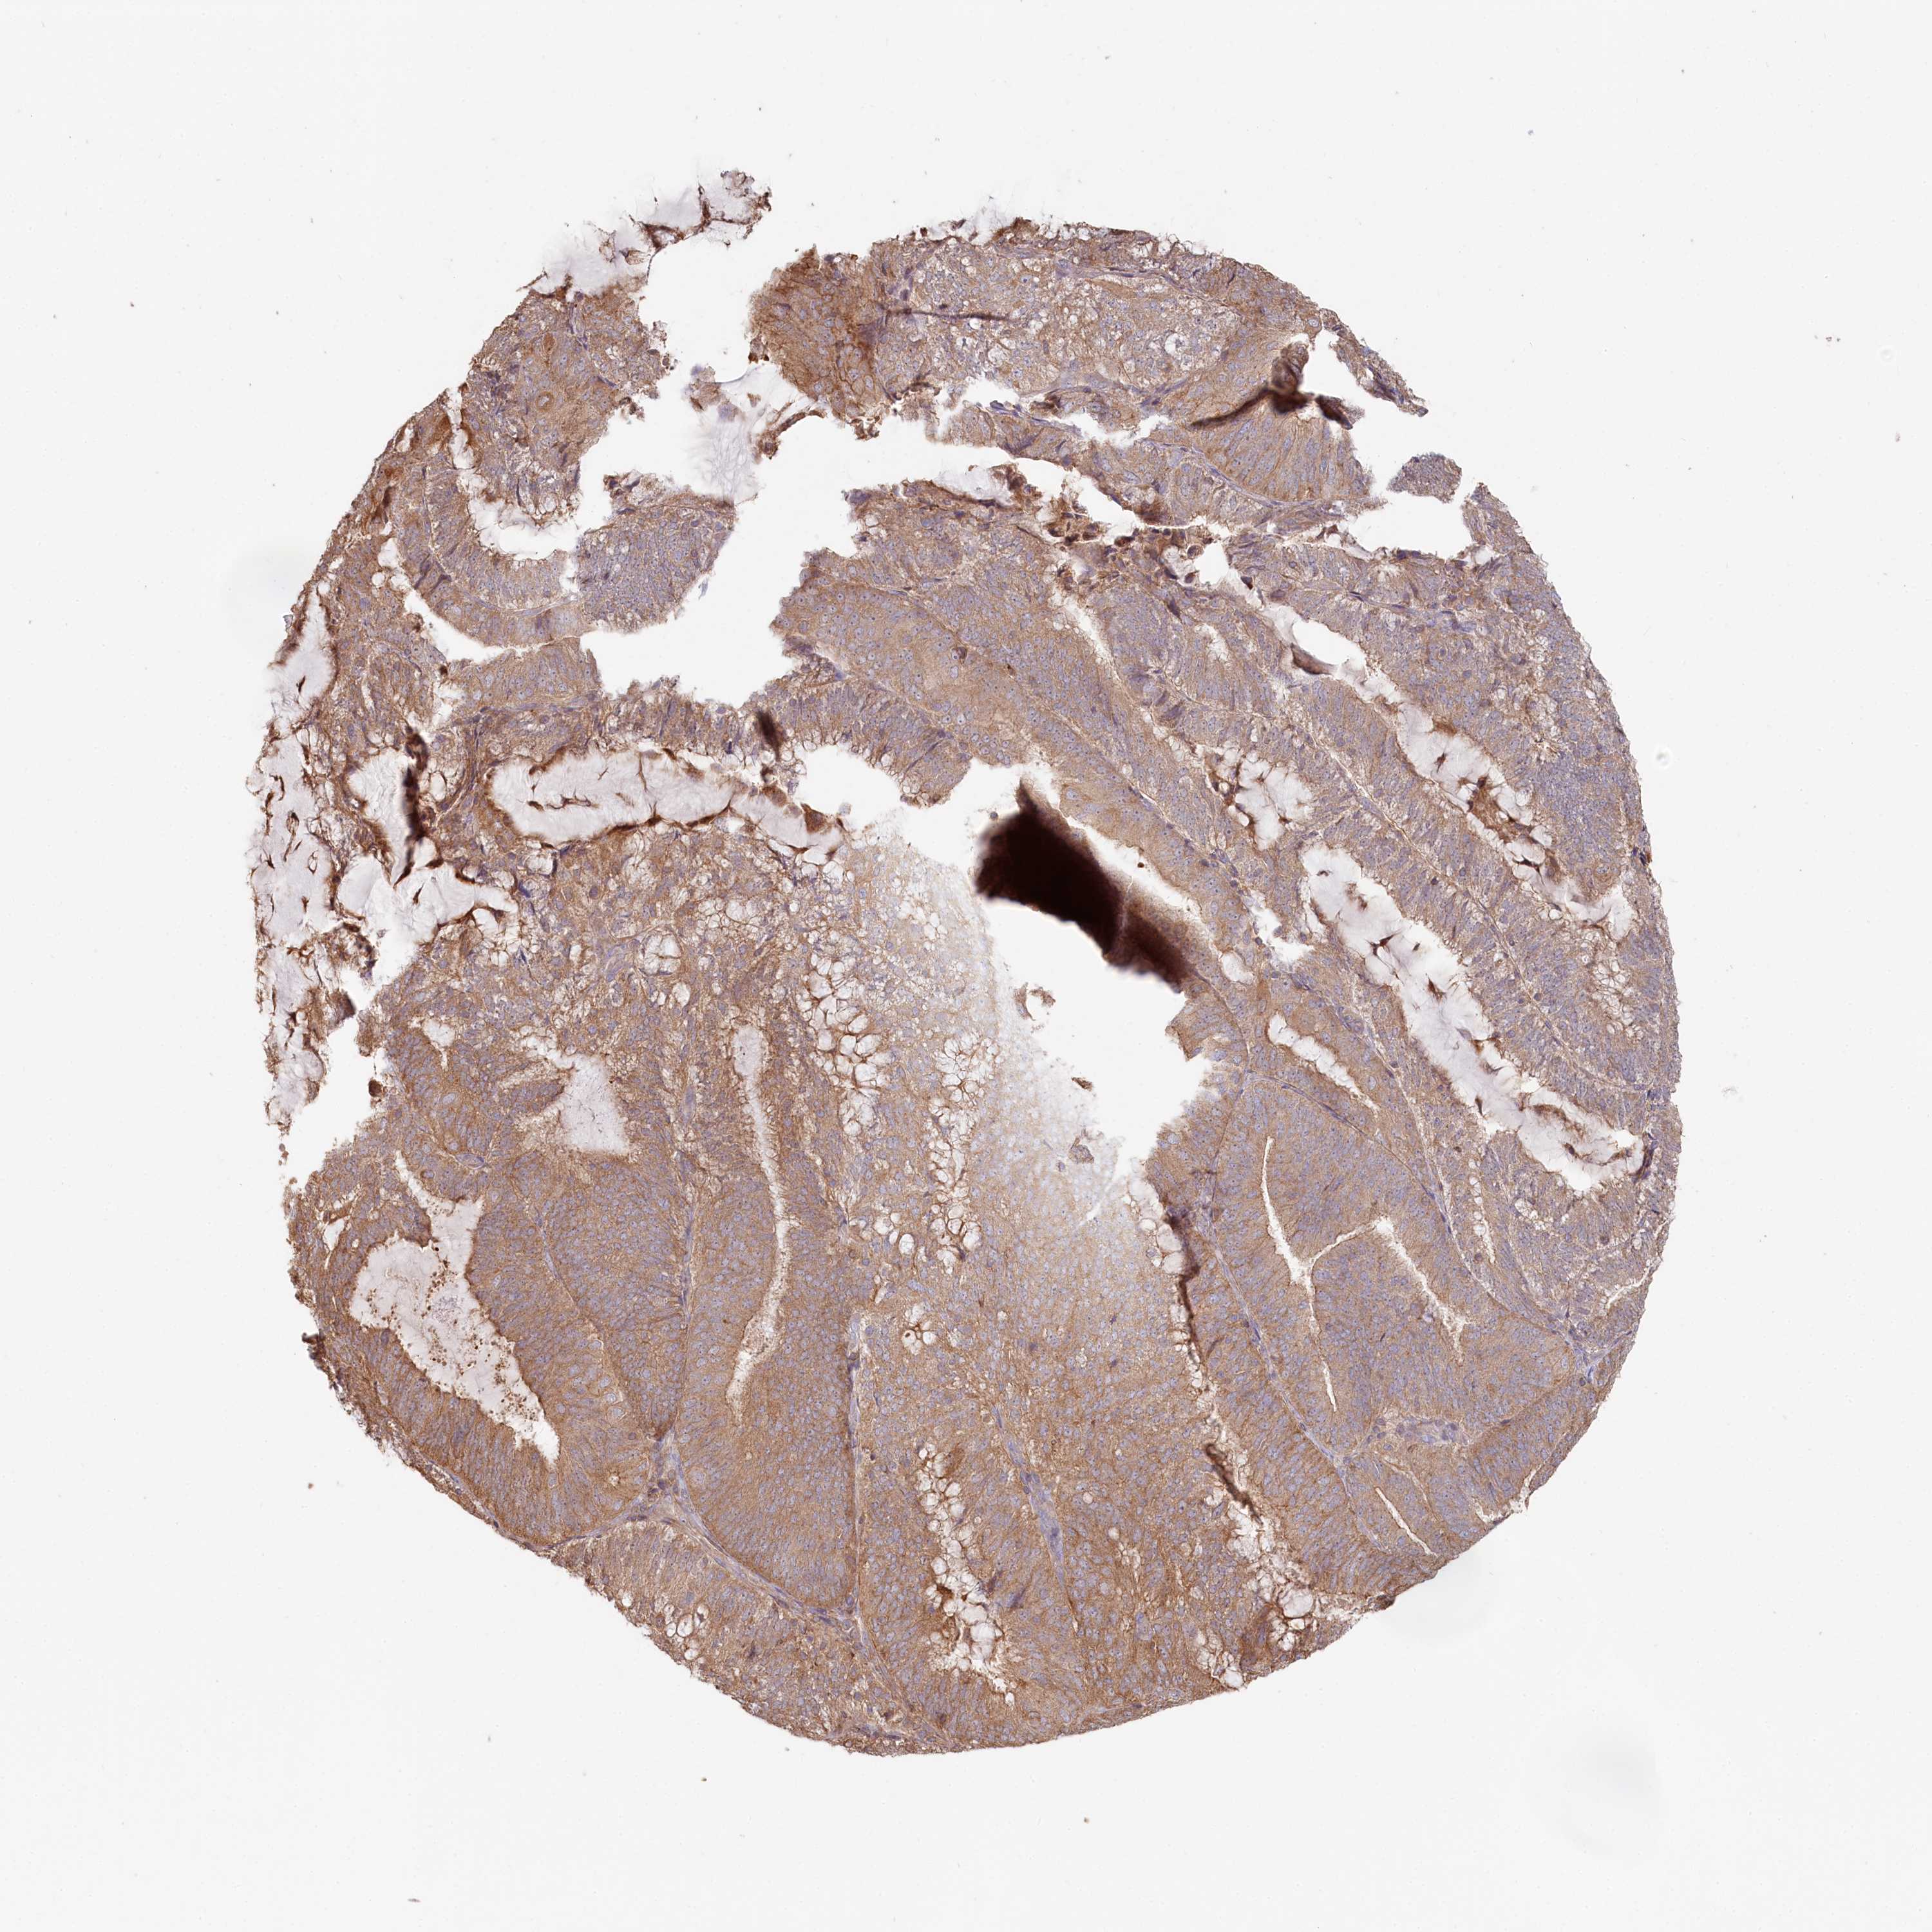

ENDOMETRIAL CANCER - Protein expressioni

A mouse-over function shows sample information and annotation data. Click on an image to view it in a full screen mode. Samples can be filtered based on level of antibody staining by selecting one or several of the following categories: high, medium, low and not detected. The assay and annotation is described here.

Note that samples used for immunohistochemistry by the Human Protein Atlas do not correspond to samples in the TCGA dataset.

Antibody stainingi

Antibody staining in the annotated cell types in the current human tissue is reported as not detected, low, medium, or high, based on conventional immunohistochemistry profiling in selected tissues. This score is based on the combination of the staining intensity and fraction of stained cells.

Each image is clickable and will lead to virtual microscopy that enables deeper exploration of all samples and also displays staining intensity scores, fraction scores and subcellular localization as well as patient and tissue information for each sample.

Antibody HPA038547

Antibody HPA038548

Staining

High

Medium

Low

Not detected

Intensity

Strong

Moderate

Weak

Negative

Quantity

>75%

75%-25%

<25%

None

Location

Nuclear

Cytoplasmic/membranous

Cytoplasmic/membranous,nuclear

Adenocarcinoma, NOS